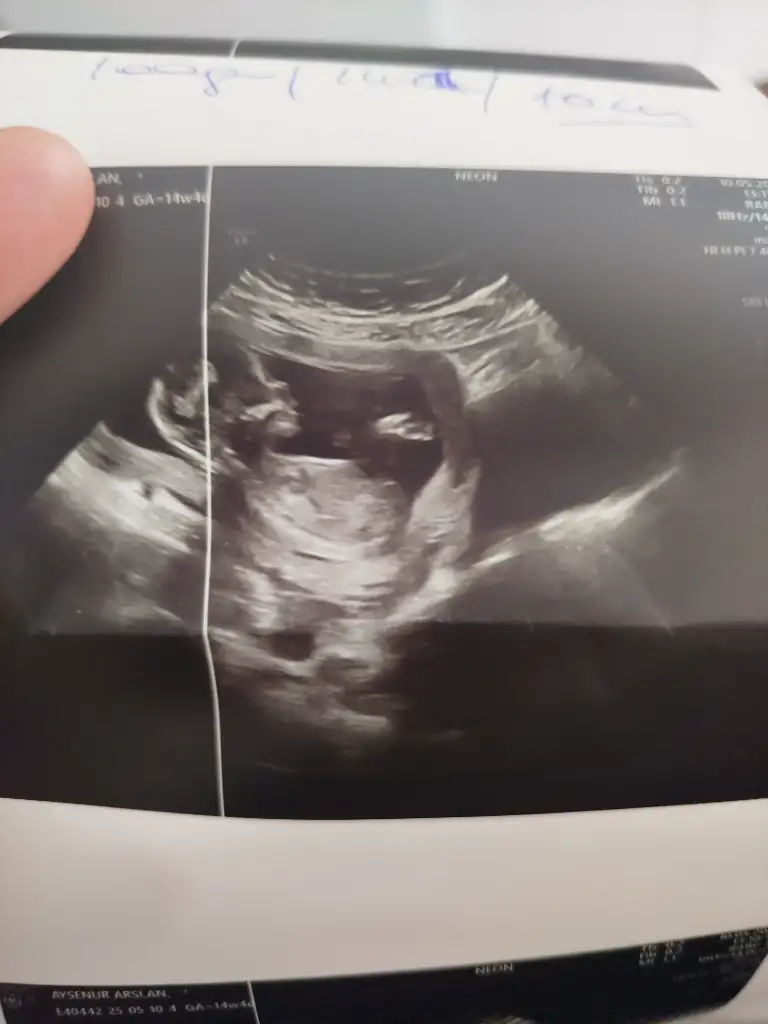

13 haftalık sizce kızmi erkekmi?

Eklentiler

• IMG_20250509_161946.webp

IMG_20250509_161946.webp

18,6 KB · Görüntüleme: 54